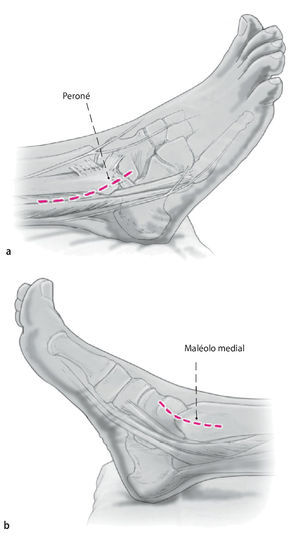

Fig. 1 Incisión lateral (a) y medial (b) . Ambas de 6-8 cm de longitud y el uso del maléolo lateral y medial como puntos de referencia.